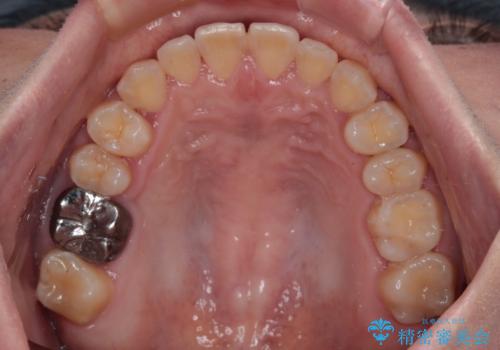

- 前歯の反対咬合を気にして来院された患者様です。

当院にて同様の咬み合わせを治療した方からのご紹介ということもあり、ご紹介者と同じワイヤー矯正で早めに治療を終えることを希望されました。

骨格的に下顎が前方に位置していましたが、歯列矯正で改善できると判断し、ワイヤー装置にて矯正治療を行うこととしました。